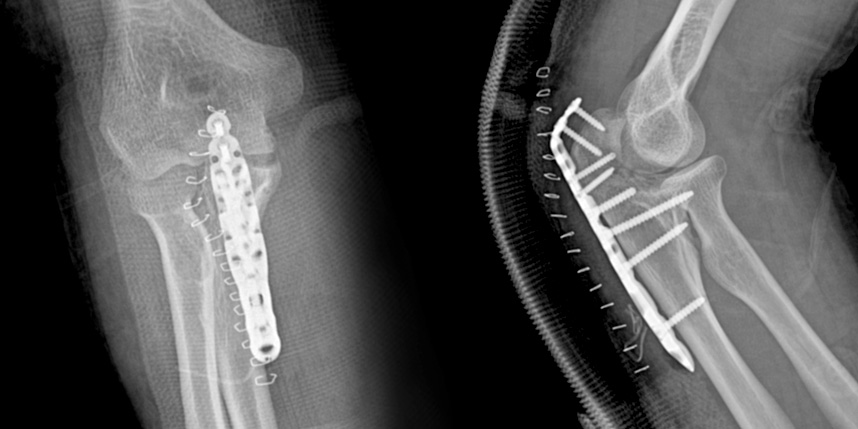

골절이 심하지 않은 경우에는 깁스로 고정해서 유합을 시킬 수 있으나, 정도가 심한 경우에는 손,발목 골절 수술을 진행할 수 있습니다.

골절은 정확하게 골절편을 잘 맞추고 고정하는 것이 중요합니다. 특히 관절면을 잘 맞추는 것이 중요합니다.

손목 골절